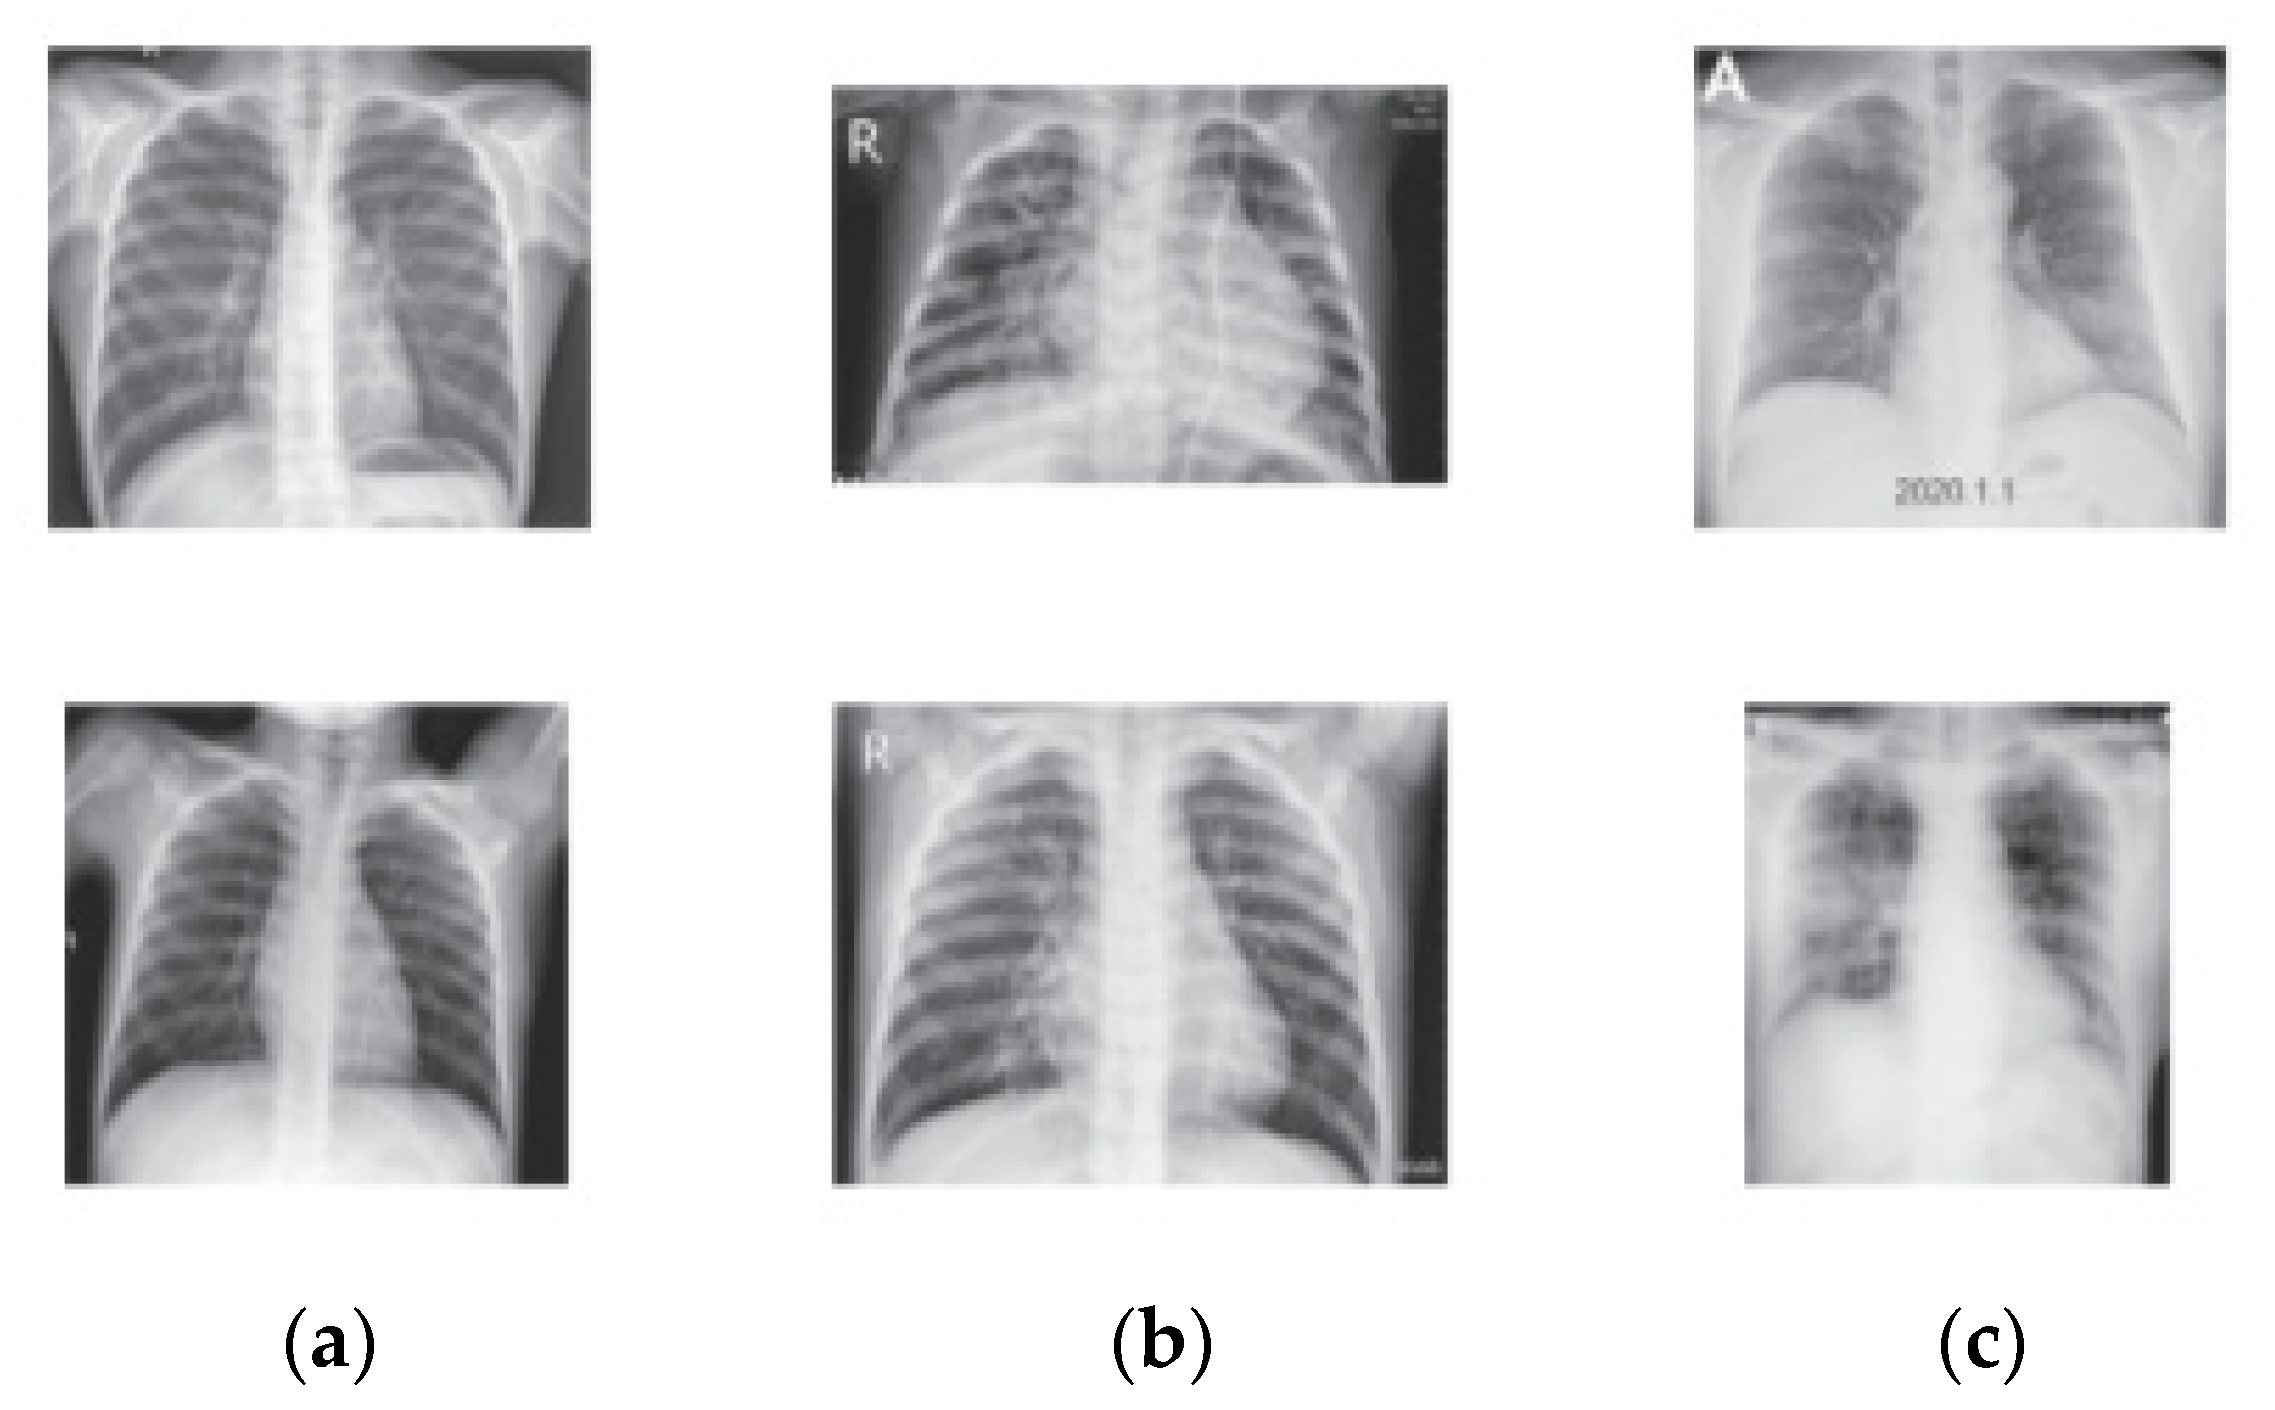

| Classes | Dataset from [53] | Dataset from [54] |

|---|---|---|

| COVID-19 | 3616 | 576 |

| Lung Opacity | 6012 | - |

| Normal | 10,200 | 1583 |

| Pneumonia | 1345 | 4273 |